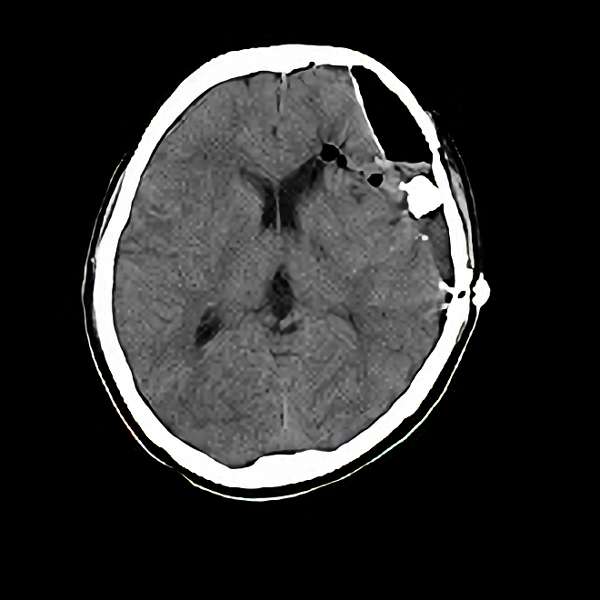

脳血管撮影

手術前

手術後